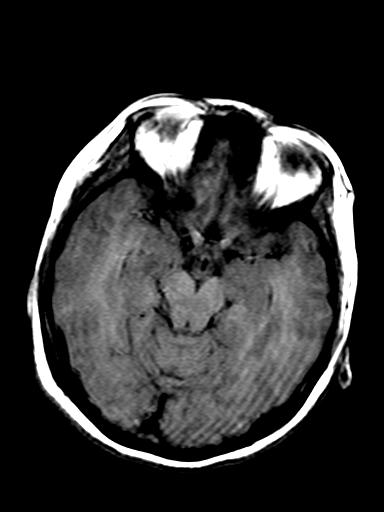

发热、头痛伴精神异常1周

脑炎,肾上腺性脑白质营养不良待除外

较对称性脑白质异常信号,深部白质t2明显低信号(铁质沉积过多?)

考虑脑白质病变,请结合临床病史及实验室检查进一步分析。